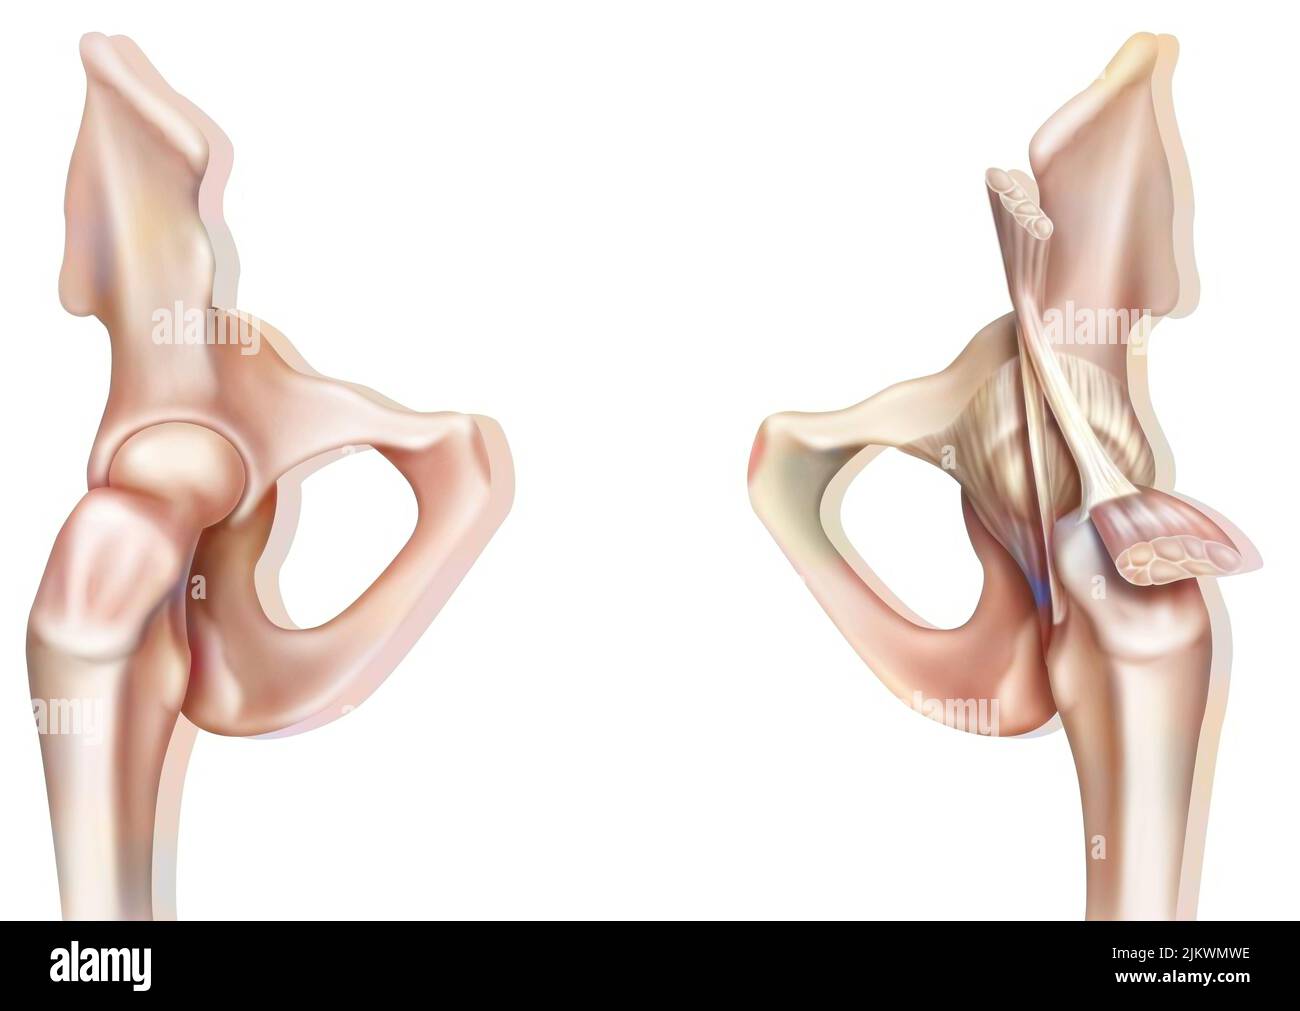

Articulation osseuse de la hanche sans et avec la capsule de l'articulation coxofémorale. Banque D'Imageshttps://www.alamyimages.fr/image-license-details/?v=1https://www.alamyimages.fr/articulation-osseuse-de-la-hanche-sans-et-avec-la-capsule-de-l-articulation-coxofemorale-image476923594.html

Articulation osseuse de la hanche sans et avec la capsule de l'articulation coxofémorale. Banque D'Imageshttps://www.alamyimages.fr/image-license-details/?v=1https://www.alamyimages.fr/articulation-osseuse-de-la-hanche-sans-et-avec-la-capsule-de-l-articulation-coxofemorale-image476923594.htmlRF2JKWMWE–Articulation osseuse de la hanche sans et avec la capsule de l'articulation coxofémorale.